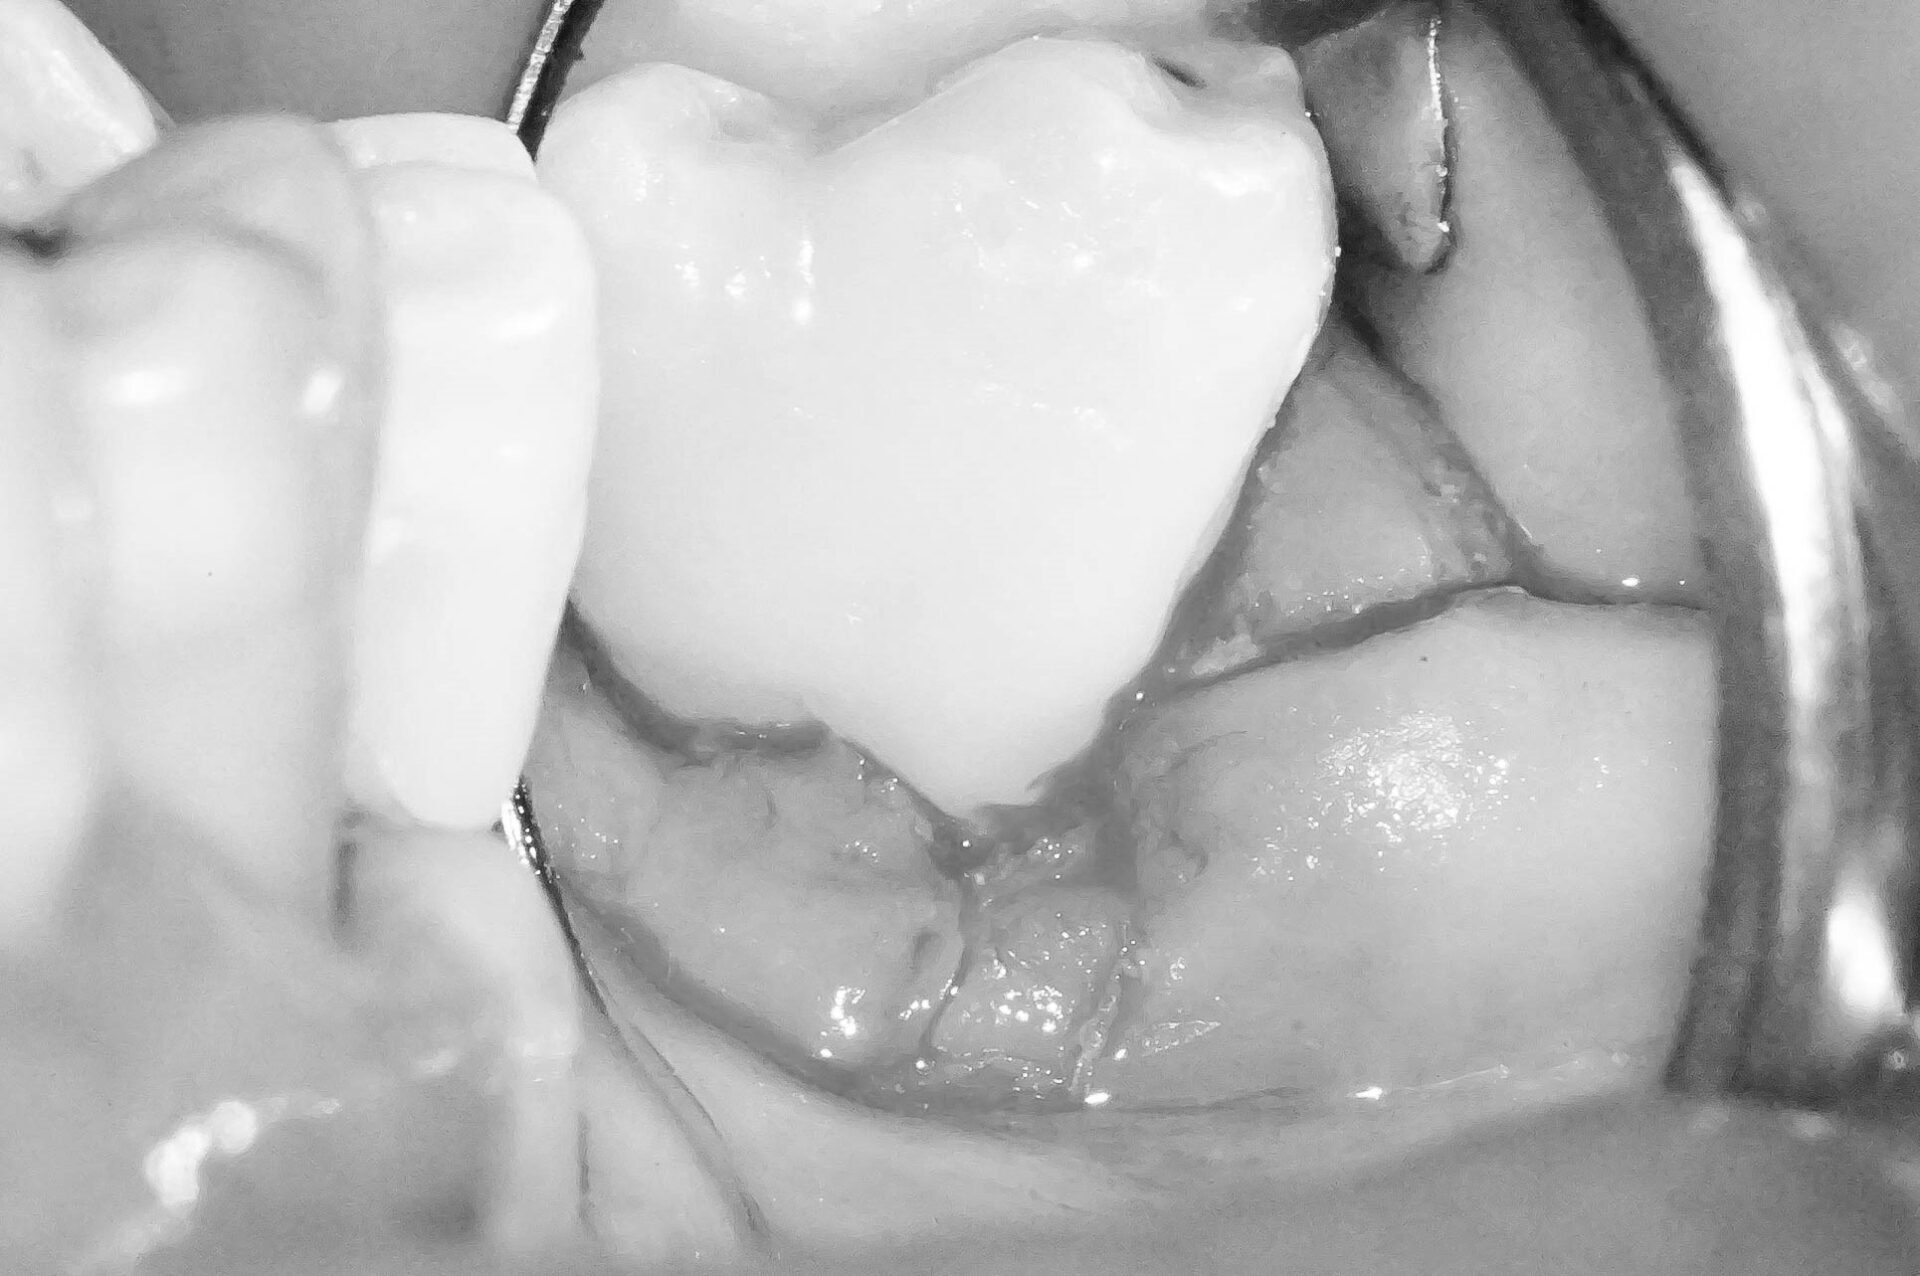

歯肉縁下ダイレクトボンディングを行った症例治療方法03

写真では分かりづらいですが、歯肉に隠れている部分に大きめのウ蝕が広がっていたので歯周外科処置を行い、視野を確保します。

レーザーで歯肉を焼き切って治療をする方法もありますが、レーザーで焼いてしまうと大きな歯肉退縮を引き起こします。

※画像はモノクロ加工しています。

歯周外科を行うことでウ蝕部分をしっかりと明示できるので、ウ蝕の取り残しをなくすことができます。

そして難易度は高いですが、その部位にラバーダムを設置します。

ラバーダムがなければ処置部位は血まみれ、唾液まみれで繊細な治療ができません。